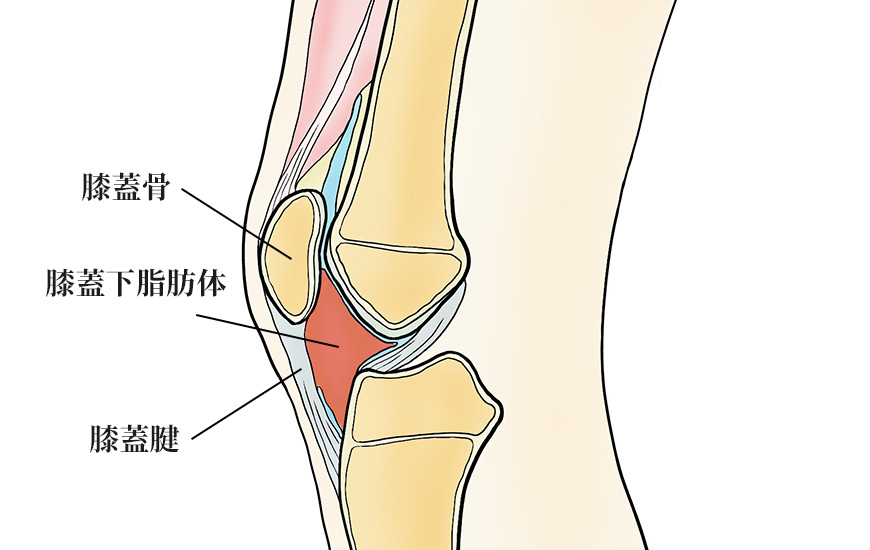

膝蓋下脂肪体炎

膝蓋下脂肪体炎は、膝蓋骨の下にある脂肪組織の炎症で、膝の前面に痛みが生じる疾患です。特に膝を伸ばす際に痛みが出る「Hoffa sign」が特徴で、押すと膝蓋骨下部に圧痛が現れます。

外傷や繰り返しの小さな負荷が主な原因とされます。診断のために、局所麻酔を脂肪体に注射し、痛みの軽減を確認することもあります。